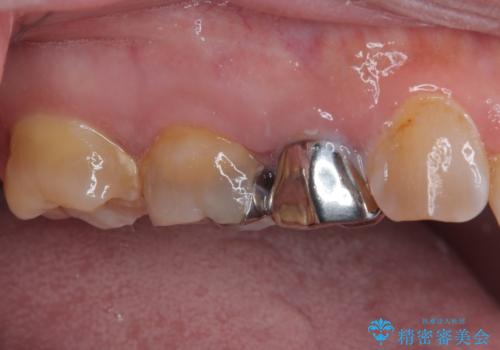

仮歯に替えた上で、速やかにオールセラミッククラウンにて補綴治療を行うこととしました。

銀歯を外したところ、土台にほとんどむし歯はなかったため、土台のやり替えを行うことなく、セラミッククラウンを装着しました。